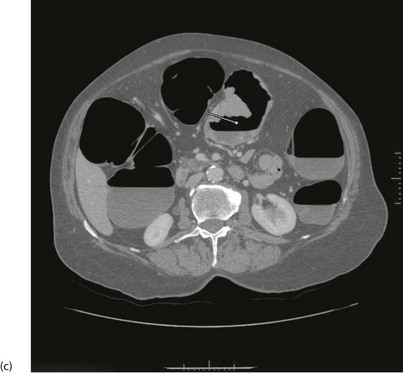

General principles of CT scanning: Computerised tomography involves X-raying a series of thin transverse ‘slices’ of the patient's head, body or limbs. A precise fan-shaped beam of X-rays is repeatedly pulsed from successive angles around the circumference of each slice and the transmitted radiation is electronically recorded on the opposite side (see Fig. 5.10).

(a) Principle of CT scanning. All images are fed into a computer and a single image of each slice produced. (b) Normal transverse CT scan. Liver L, gall bladder G, stomach St, kidneys K, aorta A, pancreas P, spleen S. (c) Normal CT scan reconstructed in the coronal plane. Liver L, bladder B, transverse colon TC, descending colon DC